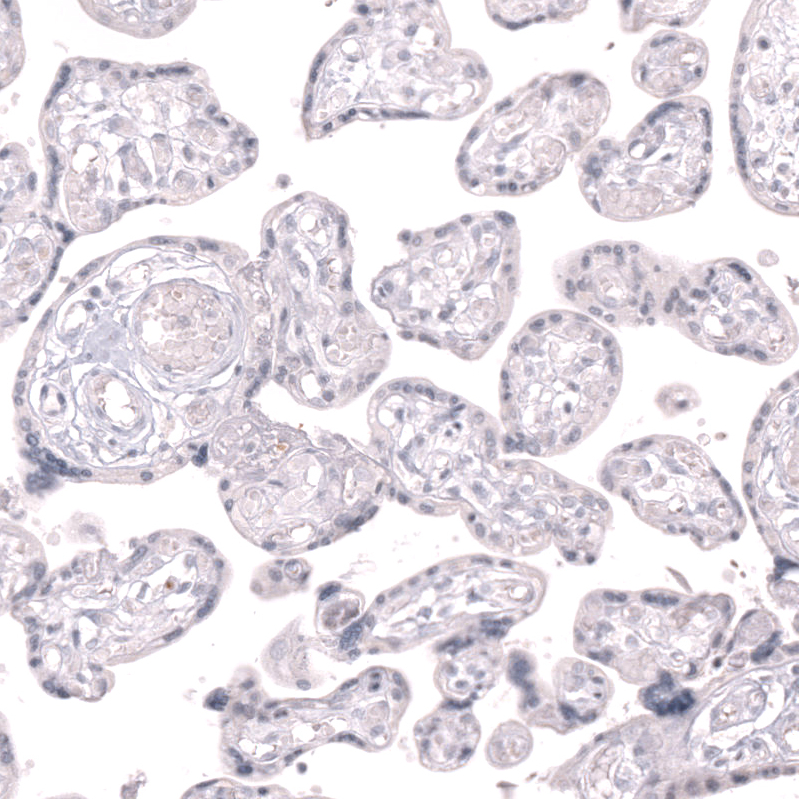

Immunohistochemistry analysis in human lymph node and placenta tissues using AMAb92049 antibody. Corresponding CLEC10A RNA-seq data are presented for the same tissues.